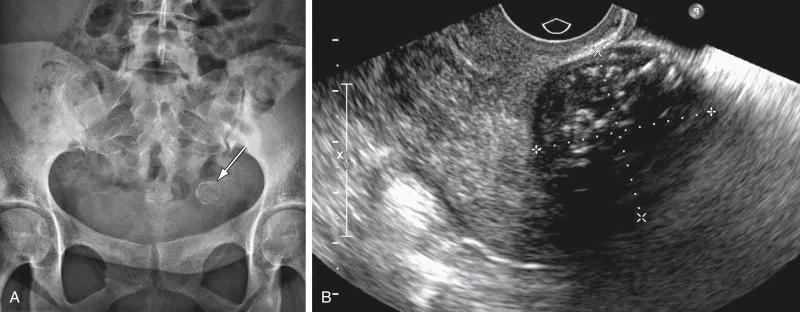

Diagnostic scan for interstitial cystitis condition